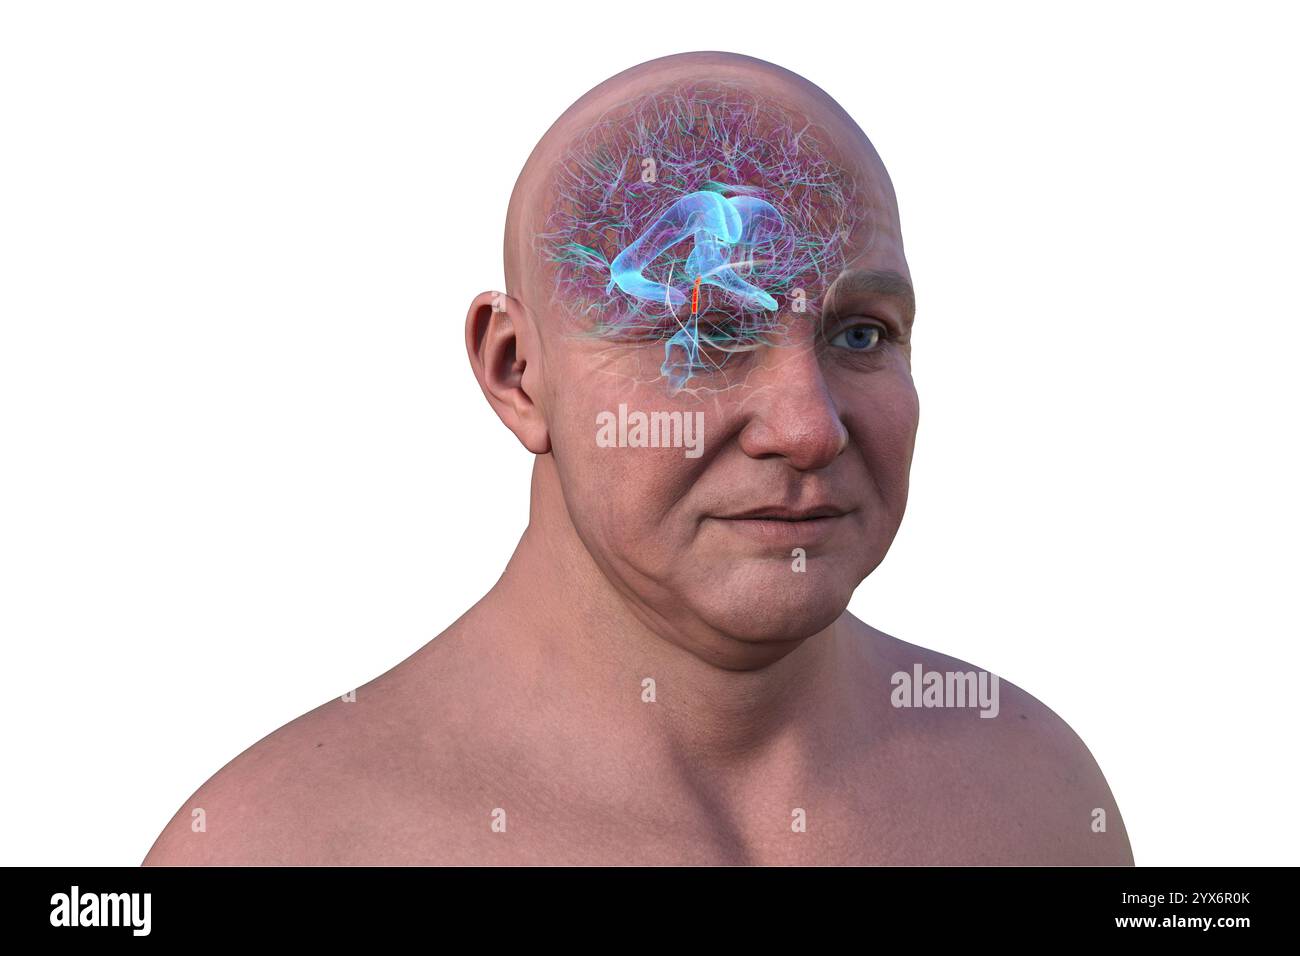

RF2YX6R0N–Computerdarstellung des menschlichen Gehirns mit orangefarbenem Aquädukt und grünem Ventrikelsystem, die den Liquorfluss (CSF) zeigen.

RF2YX6R0K–Computerdarstellung des menschlichen Gehirns mit orangefarbenem Aquädukt und grünem Ventrikelsystem, die den Liquorfluss (CSF) zeigen.

RF2YX6R02–Computerdarstellung des menschlichen Gehirns mit orangefarbenem Aquädukt und grünem Ventrikelsystem, die den Liquorfluss (CSF) zeigen.

RF2YX6R05–Computerdarstellung des menschlichen Gehirns mit orangefarbenem Aquädukt und grünem Ventrikelsystem, die den Liquorfluss (CSF) zeigen.

RF2YX6R0G–Computerdarstellung des menschlichen Gehirns mit orangefarbenem Aquädukt und grünem Ventrikelsystem, die den Liquorfluss (CSF) zeigen.